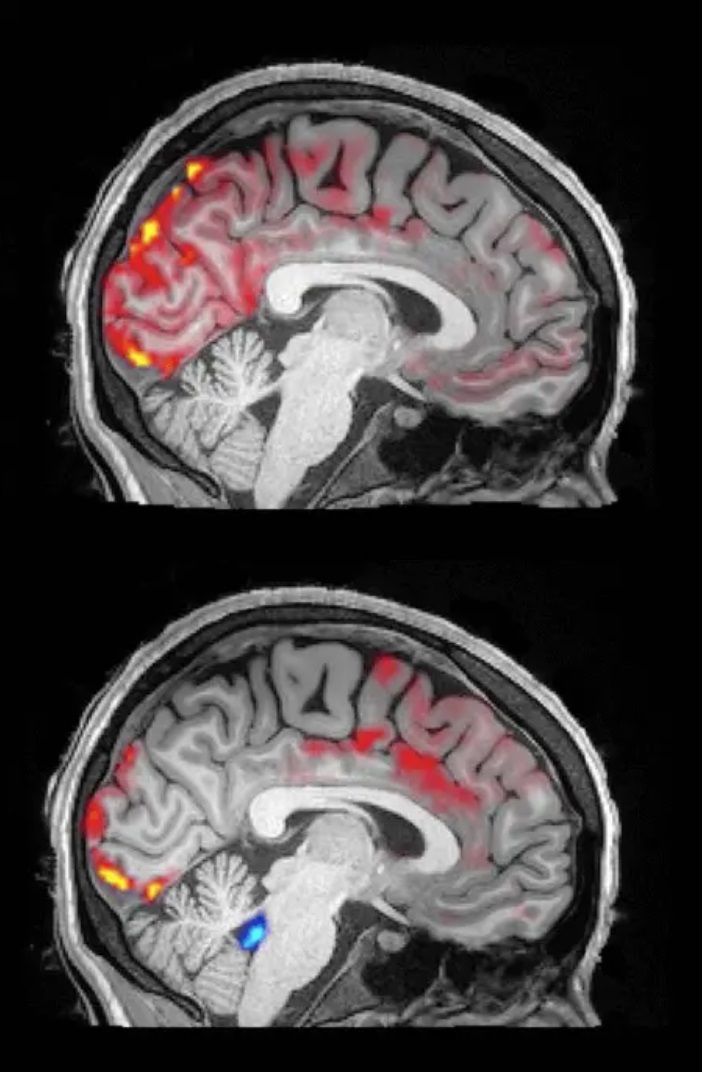

Trong khi ngủ, bạn thực sự được “làm sạch” não. Các nhà khoa học tại Đại học Boston đã ghi lại được quá trình chưa từng có này: màu đỏ là máu, màu xanh là dịch não tủy. Điều đáng chú ý là, trước đây chưa từng được phát hiện, máu định kỳ chảy ra khỏi não với số lượng lớn. Mỗi khi máu chảy ra với số lượng lớn, dịch não tủy lại tận dụng cơ hội này để phát động một đợt tấn công. Một khi đã vào đúng vị trí, dịch não tủy sẽ loại bỏ các độc tố, chẳng hạn như protein beta-amyloid gây ra bệnh Alzheimer.

Trong khi ngủ, bạn thực sự được “làm sạch” não (Ảnh: Internet)

Quá trình làm sạch này chỉ có thể đạt được sau khi ngủ, cho phép mọi người thức dậy với một bộ não sảng khoái. Khi thức dậy, dịch não tủy không có đủ cơ hội để xâm nhập. Ngoài ra, các nhà nghiên cứu cũng đã phát hiện ra mối quan hệ giữa hoạt động điện não và quá trình làm sạch, nghĩa là sóng não điều khiển sự di chuyển của dịch não tủy.

Quá trình làm sạch này chỉ có thể đạt được sau khi ngủ (Ảnh: Internet)

Trong khi ngủ, bạn thực sự được “làm sạch” não. Các nhà khoa học tại Đại học Boston đã ghi lại được quá trình chưa từng có này: màu đỏ là máu, màu xanh là dịch não tủy. Điều đáng chú ý là, trước đây chưa từng được phát hiện, máu định kỳ chảy ra khỏi não với số lượng lớn. Mỗi khi máu chảy ra với số lượng lớn, dịch não tủy lại tận dụng cơ hội này để phát động một đợt tấn công. Một khi đã vào đúng vị trí, dịch não tủy sẽ loại bỏ các độc tố, chẳng hạn như protein beta-amyloid gây ra bệnh Alzheimer.

Trong khi ngủ, bạn thực sự được “làm sạch” não (Ảnh: Internet)

Quá trình làm sạch này chỉ có thể đạt được sau khi ngủ, cho phép mọi người thức dậy với một bộ não sảng khoái. Khi thức dậy, dịch não tủy không có đủ cơ hội để xâm nhập. Ngoài ra, các nhà nghiên cứu cũng đã phát hiện ra mối quan hệ giữa hoạt động điện não và quá trình làm sạch, nghĩa là sóng não điều khiển sự di chuyển của dịch não tủy.

Quá trình làm sạch này chỉ có thể đạt được sau khi ngủ (Ảnh: Internet)